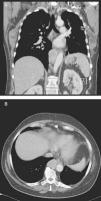

Caso clínicoUma mulher de 68 anos de idade, com história prévia de lobectomia inferior esquerda por bronquiectasia complicada por quilotórax (1994), foi submetida a uma TC de rotina (2008) que revelou uma massa no mediastino posterior inferior direito, com 5cm de diâmetro (fig. 1), que foi submetida a ressecção cirúrgica.

Perante as características morfológicas e imunohistoquímicas, o diagnóstico efetuado foi de um linfangioleiomioma ganglionar. Considerando que o envolvimento extrapulmonar exclusivo é raro5, procedemos à revisão da lobectomia, realizada 14 anos antes por bronquiectasias complicadas de quilotórax. Foi também observada uma proliferação pulmonar nodular intersticial de células fusiformes, inicialmente interpretadas como MPMNs, secundários a hipoxémia local, mas revelando diferenciação muscular com positividade para α-SMA, que não se encontra reportada nesta entidade7. Um dos gânglios linfáticos hilares também mostrava pequenas áreas musculares lisas subcapsulares com imunomarcação para HMB-45. A paciente não exibia o aspeto radiológico típico da LAM na primeira cirurgia, mostrando apenas alterações compatíveis com bronquiectasias e derrame pleural. Em 2008, apesar de ter desenvolvido dispneia de esforço, não foram reportadas alterações consistentes com envolvimento pulmonar por LAM (fig. 6). No entanto, avaliando as imagens retrospetivamente e perante um diagnóstico patológico estabelecido de linfangioleiomioma, poderão ser valorizadas de forma diferente raras lucências visíveis, algumas envolvidas por opacidades em «vidro despolido» ligeiras. Estas assemelhavam-se a quistos pulmonares (com uma parede discernível, que é contrária à hipótese de apenas se tratar de destruição pulmonar enfisematosa). Estes eram bem definidos, com pequenas dimensões, similares uns aos outros e dispersos pelos pulmões. Estas alterações são muito ligeiras, não permitindo um diagnóstico imagiológico inequívoco da doença, mas que também não devem ser ignoradas ou desconsideradas, e podem corresponder, de facto, ao comprometimento pulmonar inicial e ligeiro pela LAM. A TC abdominal mostrou também massas consistentes com dilatação de vasos linfáticos abdominais e com gânglios linfáticos aumentados (fig. 7).

Imagens TAC axiais com algoritmo de alta resolução do tórax (B, D) e imagens TAC axiais de alta resolução (A, C): algumas lucências visíveis (círculos azuis) de pequenas dimensões, semelhantes umas às outras e distribuídas ao longo dos pulmões, bem definidas com uma parede discernível, algumas delas rodeadas por ligeiras opacidades em vidro despolido (C).